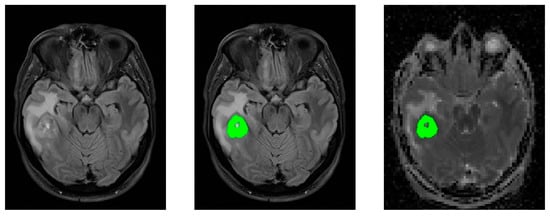

2.5. Image Post-Processing